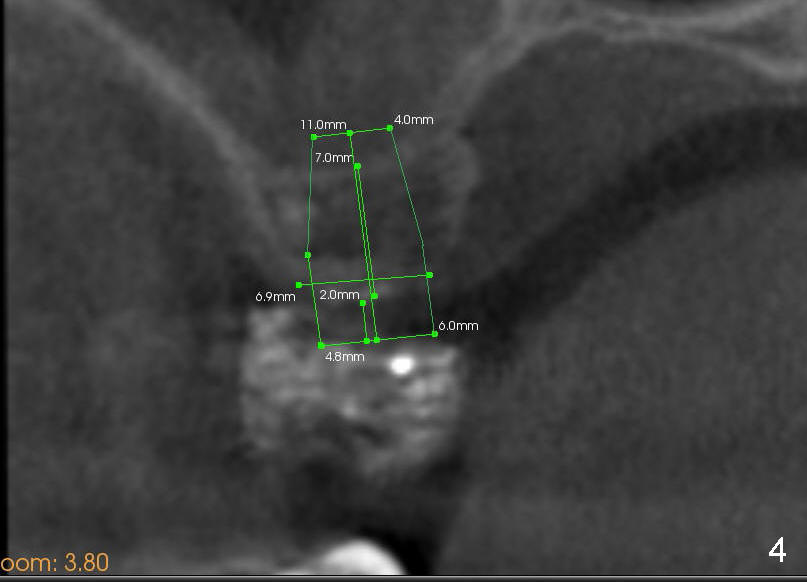

Davis is 53 years old.  This Wednesday an implant will be placed at the site of #2.  Since the case is complicated (involving multiple implant restoration), CT scan stent is fabricated using Calcium Sulphate (Fig.1 (sagittal section) S).  The stent helps treatment planning: placing 6x11 mm gingiva-level tapered implant in the most ideal restorative position (Fig.3,4 (coronal section)).  Since bone height is less than 7 mm (Fig.1), sinus lift is planned (Fig.3,4).

The method of sinus lift depends upon bone density.  A brief look at the CT scan reveals that bonedensity is high (H, Fig.1) in the dentulous area  (1st molar), medium (M) in the tuberosity and low (L) in the edentulous area (2nd molar).  The lower right of every CT planar image shows Hounsfield unit of a particular area where the mouse curse rests.  The map of bone density is shown in Fig.2.

The density of the medullar area of the edentulous is so low (10) that the sinus floor (bone density 300) has to be used for primary stability of the implant.  Additionally, an osteotome may encounter resistance when it penetrates the crest (bone density 200; a cortical plate).  Once past the crest, tapping the osteotome through the cancellous bone should be easy until reaching the sinus floor (cortex).